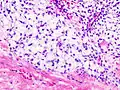

Патологическая анатомия

Хондросаркома — злокачественная опухоль хрящевого строения. Хондросаркома периферической локализации хорошо выявляется в виде плотной опухоли, прилегающей к кортикальному слою кости, иногда прорастающей в кость на различную глубину. В ней могут быть очаги оссификации и петрификаты. Опухоль плотноэластической консистенции, при наличии ослизнения, распада или кровоизлияний — более мягкая, не имеет ясного ограничения от соседней ткани. При разрезе нетрудно определить хрящевой её характер. При микроскопическом исследовании опухоль напоминает иногда хондрому, состоит из незрелых клеток с резко выраженным клеточным атипизмом. Часто рисунок опухоли имеет вид микросаркомы, в которой можно найти участки хрящевой ткани с плохо оформленными ячейками, содержащие неправильной формы хондробласты.